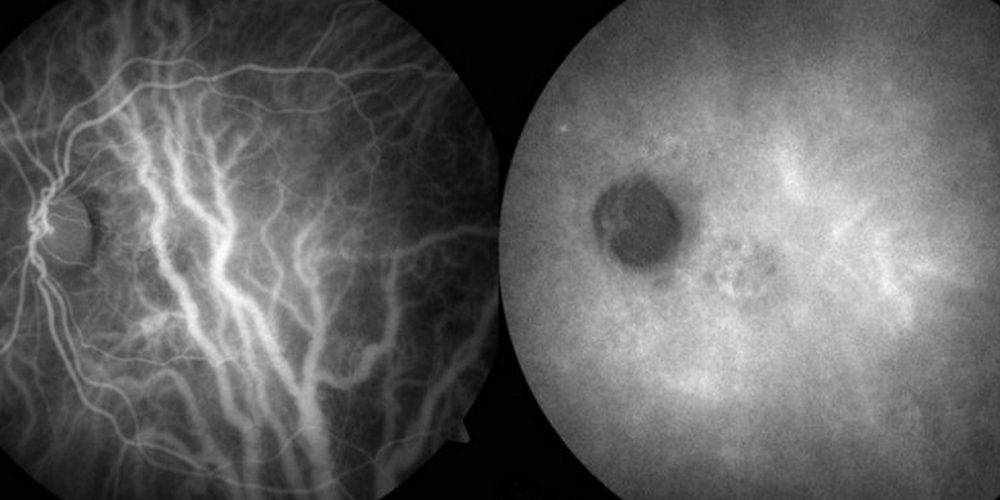

A Angiofluoresceinografia tem a função de avaliar o fluxo de sangue nas veias e artérias da retina.

São realizadas imagens do fundo de olho. Com a passagem do contraste é possível a observação detalhada dos vasos sanguíneos.